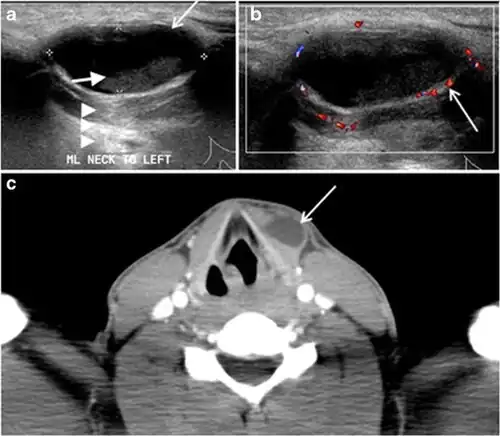

Fig. 4. A 45-year-old male patient presented with anterior mediastinal metastatic PTC lesions and occult primary on imaging. Histopathology examination of the resected thyroid gland revealed micro-foci of PTC; the largest, in the isthmus, measured 4 mm. a transverse greyscale ultrasound of the thyroid demonstrates homogeneous gland with normal echogenicity and size. No focal lesion or micro-calcifications. b Non-enhanced CT scan obtained as part of PET/CT examination shows a heterogeneous, large, relatively dense anterior mediastinal mass (white arrow) with peripheral calcification (arrowheads). Thyroid gland has normal CT appearance with no abnormal FDG uptake (not shown).[1] -